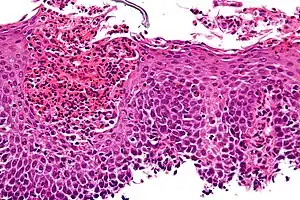

The esophagus is a muscular tube made of both voluntary and involuntary muscles. It is responsible for peristalsis of food. It is about 8 inches long and passes through the diaphragm before entering the stomach. The esophagus is made up of three layers: from the inside out, they are the mucosa, submucosa, muscularis externa. The mucosa, the inner most layer and lining of the esophagus, is composed of stratified squamous epithelium, lamina propria, and muscularis mucosae. At the end of the esophagus is the lower esophageal sphincter, which normally prevents stomach acid from entering the esophagus.

If the sphincter is not sufficiently tight, it may allow acid to enter the esophagus, causing inflammation of one or more layers. Esophagitis may also occur if an infection is present, which may be due to bacteria, viruses, or fungi; or by diseases that affect the immune system.[4]